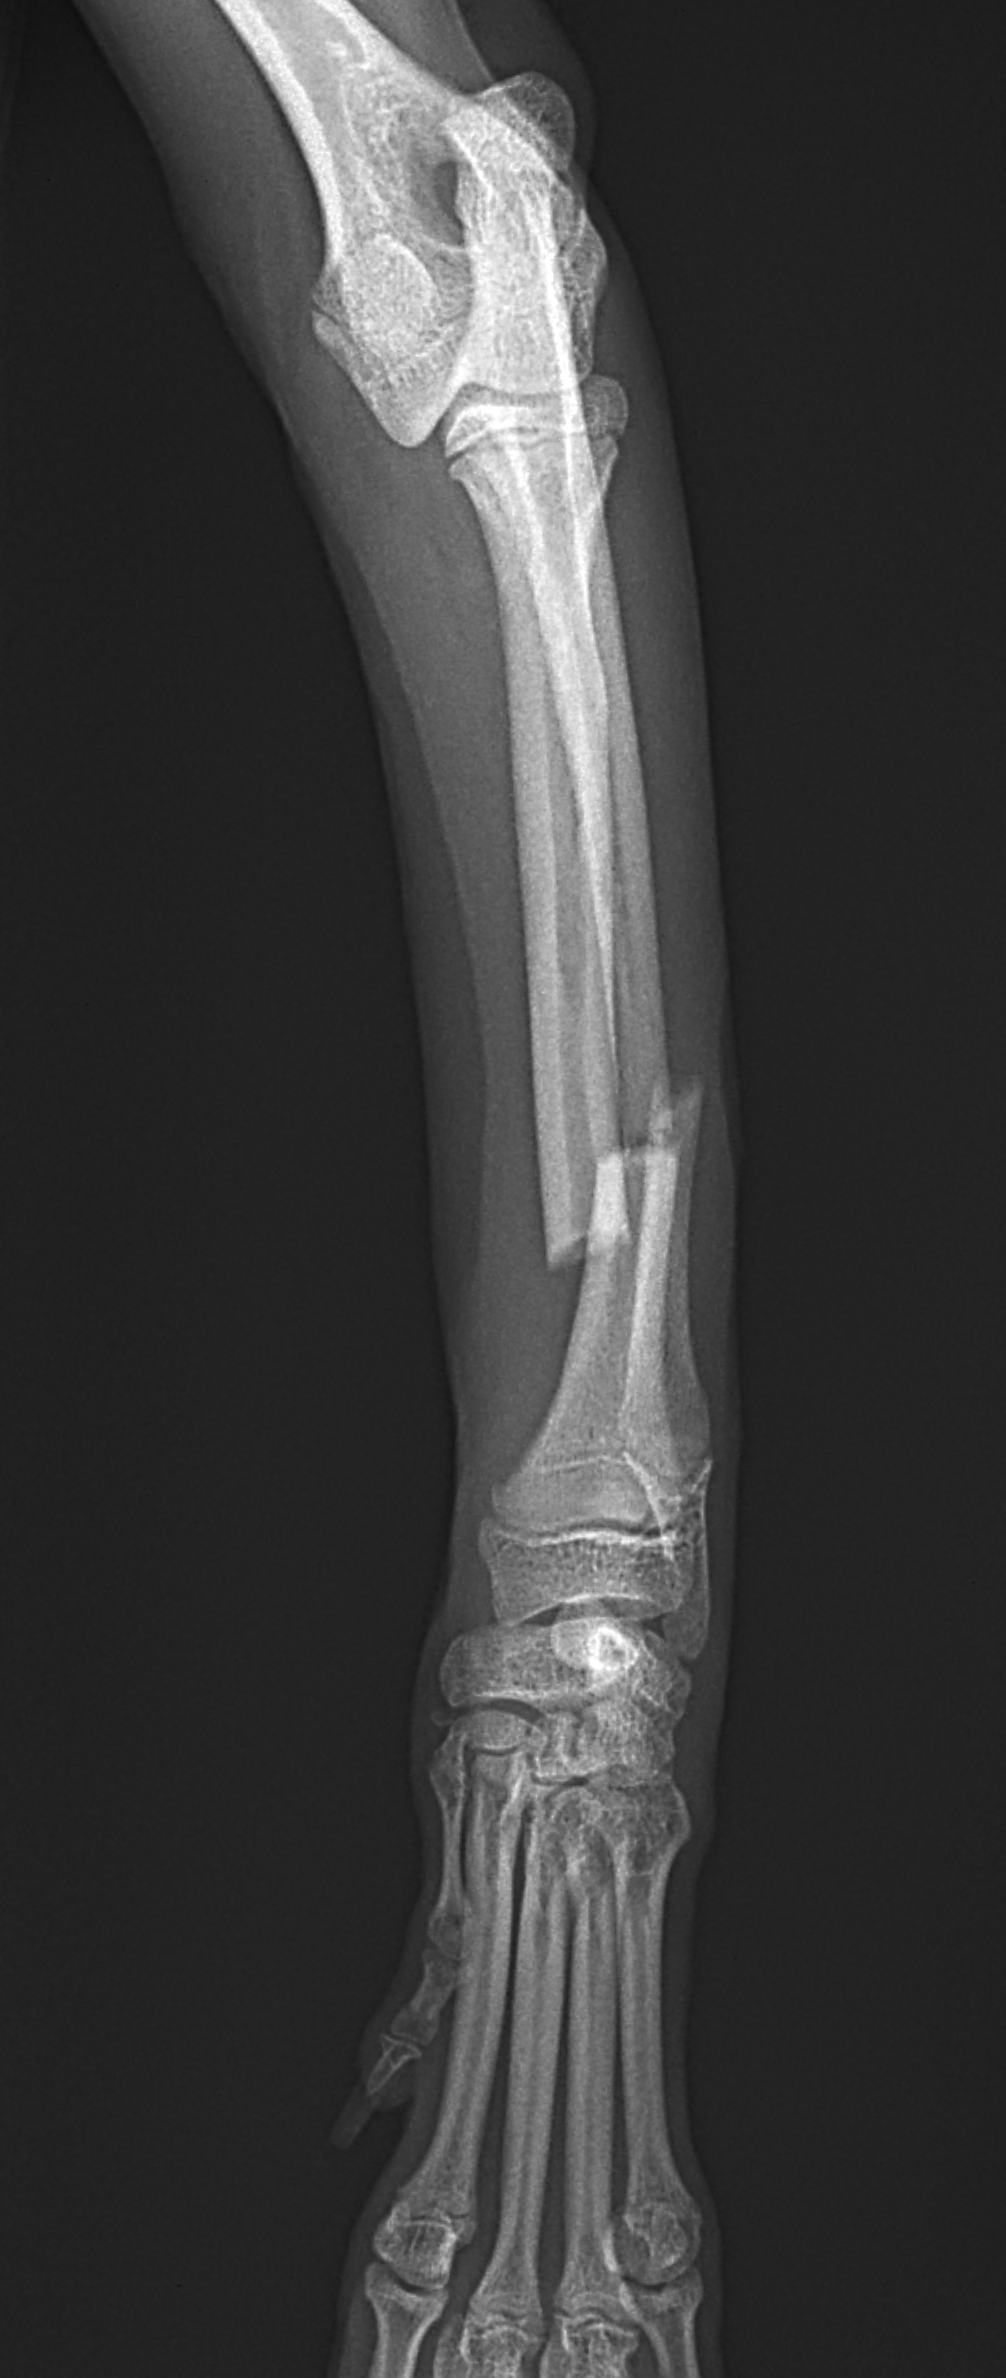

橈骨固定術 #241 Toy Poodleさん(7ヶ月齢)が室内で骨幹中央部からやや遠位の橈骨骨折をしたとの事。1.5コンベンショナルプレートで整復しました。しばらく安静が必要です。 症例カテゴリー 放射線治療整形外科軟部組織外科脳神経外科内科腫瘍外科救急・集中治療リハビリテーション科腫瘍内科内視鏡科脳神経科呼吸器外科中医・漢方猫の腎移植循環器科